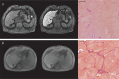

Objective: To evaluate the influence of an active inflammatory process in the liver on Gd-EOB-DTPA-enhanced MR imaging in patients with different degrees of fibrosis/cirrhosis.

Material and methods: Overall, a number of 91 patients (61 men and 30 women; mean age 58 years) were included in this retrospective study. The inclusion criteria for this study were Gd-EOB-DTPA-enhanced MRI of the liver and histopathological evaluation of fibrotic and inflammatory changes. T1-weighted VIBE sequences of the liver with fat suppression were evaluated to determine the relative signal change (RE) between native and hepatobiliary phase (20min). In simple and multiple linear regression analyses, the influence of liver fibrosis/cirrhosis (Ishak score) and the histopathological degree of hepatitis (Modified Hepatic Activity Index, mHAI) on RE were evaluated.

Results: RE decreased significantly with increasing liver fibrosis/cirrhosis (p < 0.001) and inflammation (mHAI, p = 0.004). In particular, a correlation between RE and periportal or periseptal boundary zone hepatitis (moth feeding necrosis, mHAI A, p = 0.001) and portal inflammation (mHAI D, p < 0.001) was observed. In multiple linear regression analysis, both the degree of inflammation and the degree of fibrosis were significant predictors for RE (p < 0.01).

Conclusion: The results of this study suggest that the MR-based hepatic enhancement index RE is not only influenced by the degree of fibrosis, but also by the degree of inflammation.